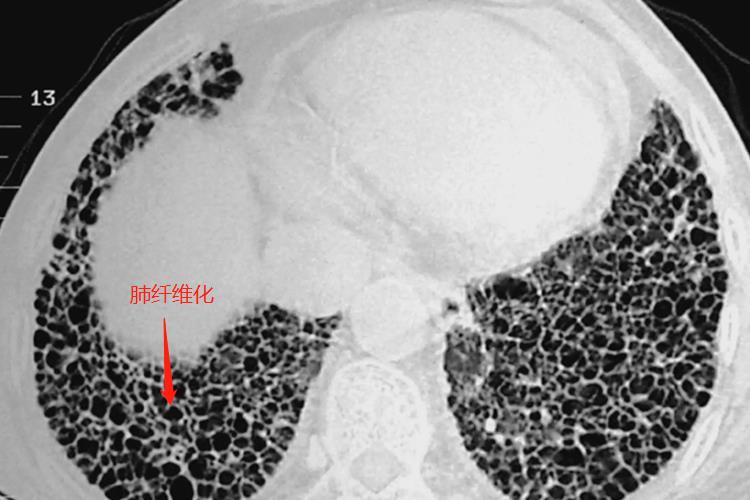

肺纤维化在CT影像学的表现主要是蜂窝肺、网格状阴影以及牵拉性支气管扩张,有时会伴随有其他形式的病变,如与磨玻璃影等。

CT在诊断肺纤维化中具有重要的价值,特征性表现为胸膜下和肺基底部的网格状阴影和蜂窝影,常伴有牵张性支气管扩张,尤其是蜂窝影;高分辨率CT上的蜂窝影指成簇的囊泡样气腔,蜂窝壁边界清楚。囊泡直径在3-10mm,偶尔可大至25mm。磨玻璃影常见,但病变范围少于网格状影。